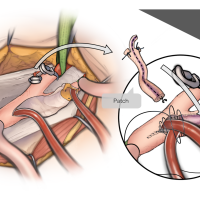

術後イラストシリーズ